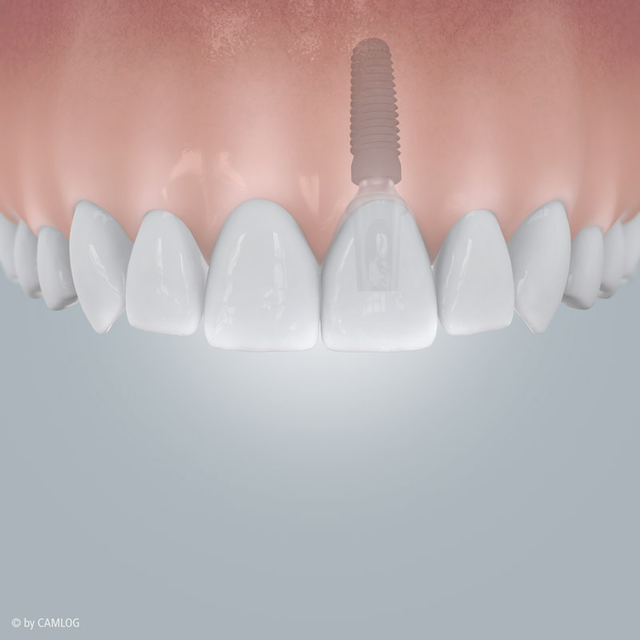

OH JE, EIN ZAHN FEHLT

Schnell kann es gehen!

Ein Unfall beim Sport oder ein Sturz im Alltag und plötzlich fehlt ein Zahn. Implantate sind hier eine schnelle und einfache Lösung – “naturnah” und unsichtbar. Fühlt sich an wie Ihr natürlicher Zahn und funktioniert auch genau so. Die kleinen und leistungsstarken Titan-Schrauben von Camlog übernehmen die Aufgaben Ihrer ursprünglichen Zahnwurzel. Darauf wird Ihre neue individuelle Zahnkrone befestigt. So ist alles wieder an seinem Platz – ganz natürlich, als wäre nichts gewesen.

Sind Implantate einmal eingesetzt, nehmen sie genau die Position Ihres natürlichen Zahns ein. Insbesondere auch da, wo es nicht direkt sichtbar wird: Camlog Implantate sind der natürlichen Zahnwurzel nachempfunden. So werden Knochen und Zahnfleisch richtig belastet und ausgeformt. Gesunde Zähne bleiben grundsätzlich unberührt und müssen nicht wie bei einer festsitzenden Brücke abgeschliffen werden. Es sind auch keine Metallklammern um benachbarte Zähne als zusätzliche Befestigung nötig, wie beispielsweise bei herausnehmbaren Teilprothesen. Bei Implantaten ist all dies überflüssig – eben rundum eine gelungene Lösung.

Auffällige Zahnlücke: Nach Zahnverlust

Lückenlos versorgt, mit einem Implantat